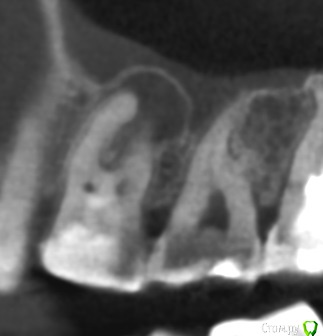

vse32 Опубликовано 8 ноября, 2019 Поделиться Опубликовано 8 ноября, 2019 16 зуб.Тему немного обсудили с хирургами на счет правильной имплантации. Появилось мнение, что реально добиться хорошего результата только эндодонтией. Я имею сомнения на этот счет. Вернее, 50 на 50.Что бы Вы выбрали? Эндодонтическое лечение или сразу имплантация. Ссылка на комментарий

annda Опубликовано 11 ноября, 2019 Поделиться Опубликовано 11 ноября, 2019 Отличный кейс для апикалки щечных корней. Купол кисты - это фактически синус лифтинг, там ведь тоненькая косточка. Если суметь это сохранить и за счет апикалки вырастить там кость, то даже в будущем будет профит немалый 1 Ссылка на комментарий